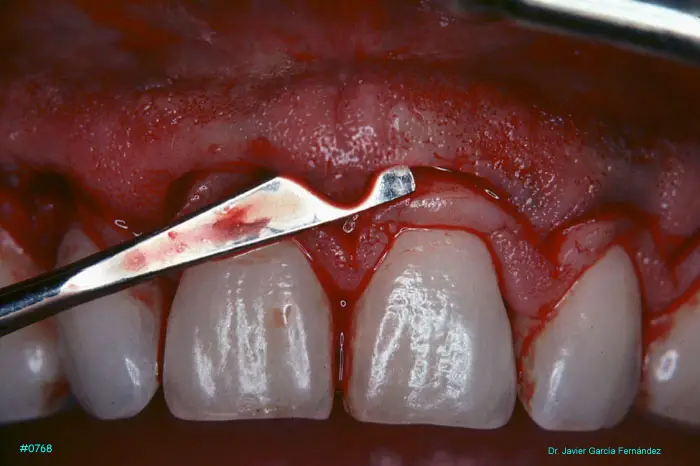

Atlas of Surgical Techniques in Periodontics. Chapter III. Atlas de Técnicas Quirúrgicas en Periodoncia